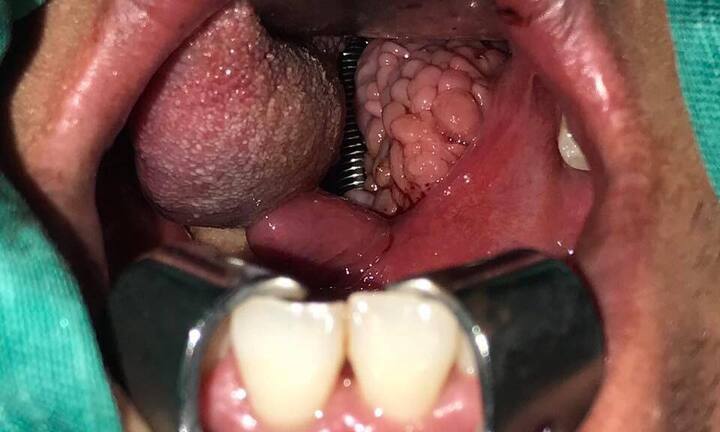

Phần amidal bị viêm nặng, sưng tấy đỏ sần sùi, nổi cục như chùm nho chèn kín đường thở người đàn ông 35 tuổi, anh này phải đi cấp cứu vì ngạt không thở được.